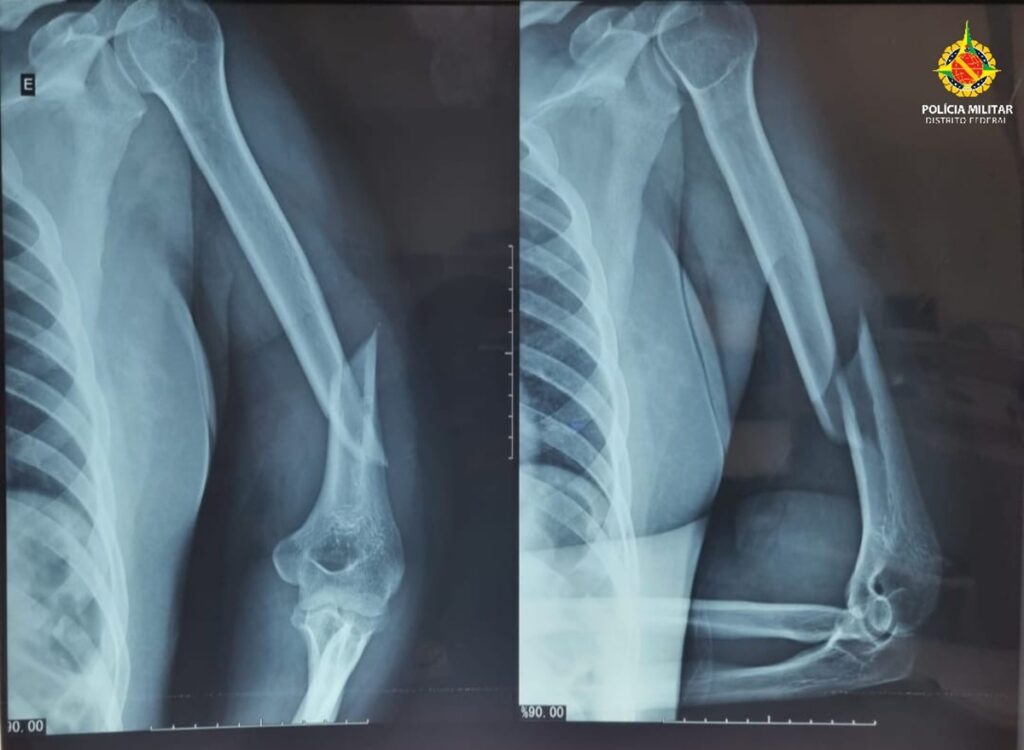

Segundo a Polícia Militar do DF (PMDF), uma equipe foi acionada para atender uma ocorrência de violência doméstica e, no local, constatou que a vítima apresentava hematomas no rosto, inchaço ao redor dos olhos, sangramento pelos ouvidos, fratura no úmero esquerdo e luxação no ombro esquerdo.